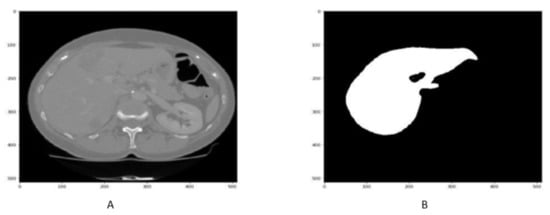

4.2. Liver Segmentation Results

The qualitative and quantitative result of liver CT scan segmentation is shown in Figure 7 and in Table 2. The proposed technique has been obtained regarding liver segmentation as assessed by DSC, accuracy, precision, specificity VOE, and RVD values. The Figure 7A,B and Table 2 highlight the better performance of proposed approach.

Figure 7.

Figure shows that the samples of Liver segmentation in (A,B).